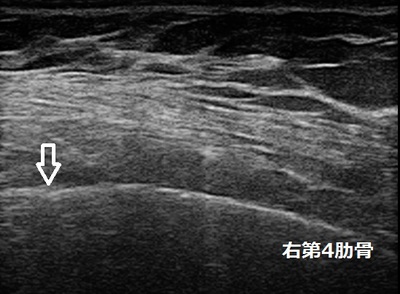

坂戸市 主婦 右胸/腕の付け根の痛み 肋骨、前鋸筋損傷

坂戸市 60代主婦。 右胸/右腕付け根の痛み、右第4肋骨、前鋸筋損傷。

1週間後に来院され、前後や横から右腕を挙げようとすると痛みます。超音波検査では右第4肋骨の骨表面が

画像矢印の箇所で凹み、肋骨上部の前鋸筋が引き伸ばされ損傷していることが認められました。

肋骨の骨癒合と筋肉の修復が促進される治療機器を使用します。家事仕事中はさらしを巻いて固定します。

3週後の治癒を目指して施術を継続中です。